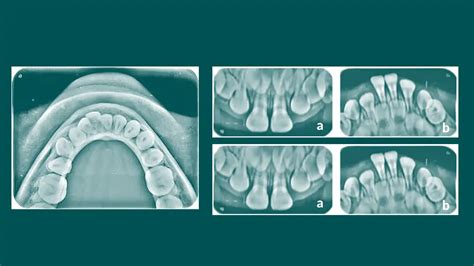

Radiografía Oclusal: Un Examen Detallado

La radiografía oclusal es una herramienta esencial en el campo de la odontología, utilizada para diagnosticar diversos problemas que afectan a los maxilares. Este tipo de prueba permite obtener imágenes claras y detalladas de la estructura dental, facilitando la identificación de lesiones, fracturas y otros problemas estomatológicos.

Se trata de una técnica de imagenología que utiliza rayos X para capturar una vista amplia de la boca. Este tipo de radiografía se coloca en la parte superior o inferior de la boca y permite visualizar tanto los dientes como los huesos maxilares en una sola toma. El término oclusal se refiere al conjunto de superficies de los dientes que contactan cuando la boca está cerrada. Esta es la zona donde la dentadura superior y la inferior se unen en la oclusión.

La radiografía oclusal es un tipo de imagen intraoral que permite ver las estructuras óseas de los maxilares. Se utiliza para localizar raíces retenidas, sialolitos, lesiones y evaluar fracturas maxilares o mandibulares.

Se utiliza principalmente para detectar dientes no erupcionados, cuerpos extraños, fracturas y, en general, evaluar la salud de los maxilares. Gracias a su enfoque, se obtienen imágenes que muestran una gran área de la boca, lo que es muy útil para los odontólogos.

Tipos de radiografías oclusales

Existen varios tipos de radiografías oclusales que se utilizan en función de la necesidad clínica:

- Radiografía oclusal anterior. Muestra los dientes anteriores y parte de los maxilares.

- Radiografía oclusal posterior. Se enfoca en los dientes posteriores y permite visualizar los molares y premolares.

- Radiografía oclusal infantil. Ha sido diseñada para el uso en niños, ajustando la película a sus necesidades.

Estas variaciones permiten a los odontólogos elegir la opción más adecuada según el diagnóstico que necesiten realizar. Las radiografías oclusales son fundamentales para obtener una visión completa de la boca y sus estructuras.